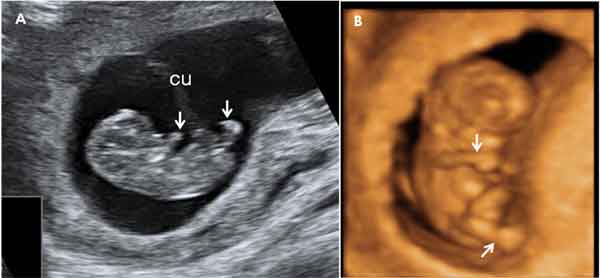

Ecografía en 2D y 3D de embarazo de 9,4 semanas

El embrión mide 24 milímetros. Cada vez tiene más forma humana. Ecografía 2D (A), con el polo cefálico y las extremidades. Ecografía 3D (B), donde se aprecian con mucha mayor claridad las estructuras fetales.

Ecografía en 2D y 3D de embarazo de 9,5 semanas.

El embrión mide 26 milímetros. Las extremidades están bastante desarrolladas (flechas), aunque todavía no pueden individualizarse los dedos. cu: cordón umbilical.